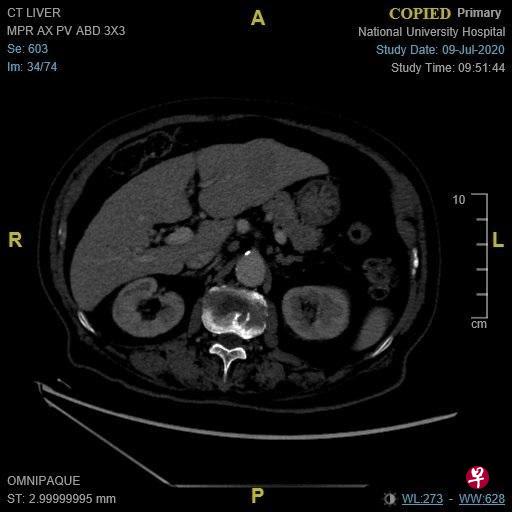

当然,对病人来说,在肝脏里发现硬块都不会是好消息。肾科的同事迅速联络我,看看是否可以尽早会诊。如果要通过正常管道安排门诊,可能须等上两周至一个月。面对患有肿瘤的病人,我们通常都会尽快安排以便提早治疗。由于超声波只是初步检查,他必须做更详细的扫描。我们马上安排了电脑断层扫描,但是老翁的慢性肾病必须加以关注,他入院吊了点滴,做了扫描。入院时,老翁有一女士陪伴。切问之下,女士是老翁友人,对他的病情非常了解,也对他照顾有加。扫描结果确诊了,老翁患有原发性肝癌(图A)。面对确诊结果,两人非常坦然,询问了治疗的选择。

上星期,病人及友人来复诊,他行动自如,声音响亮,中气十足。我们也安排了扫描检查肝肿瘤治疗后的成果,肿瘤已经完全消灭(图B),可喜可贺!病人的友人非常激动,走出门诊室后,又再次折返鞠躬道谢!真令人感动。